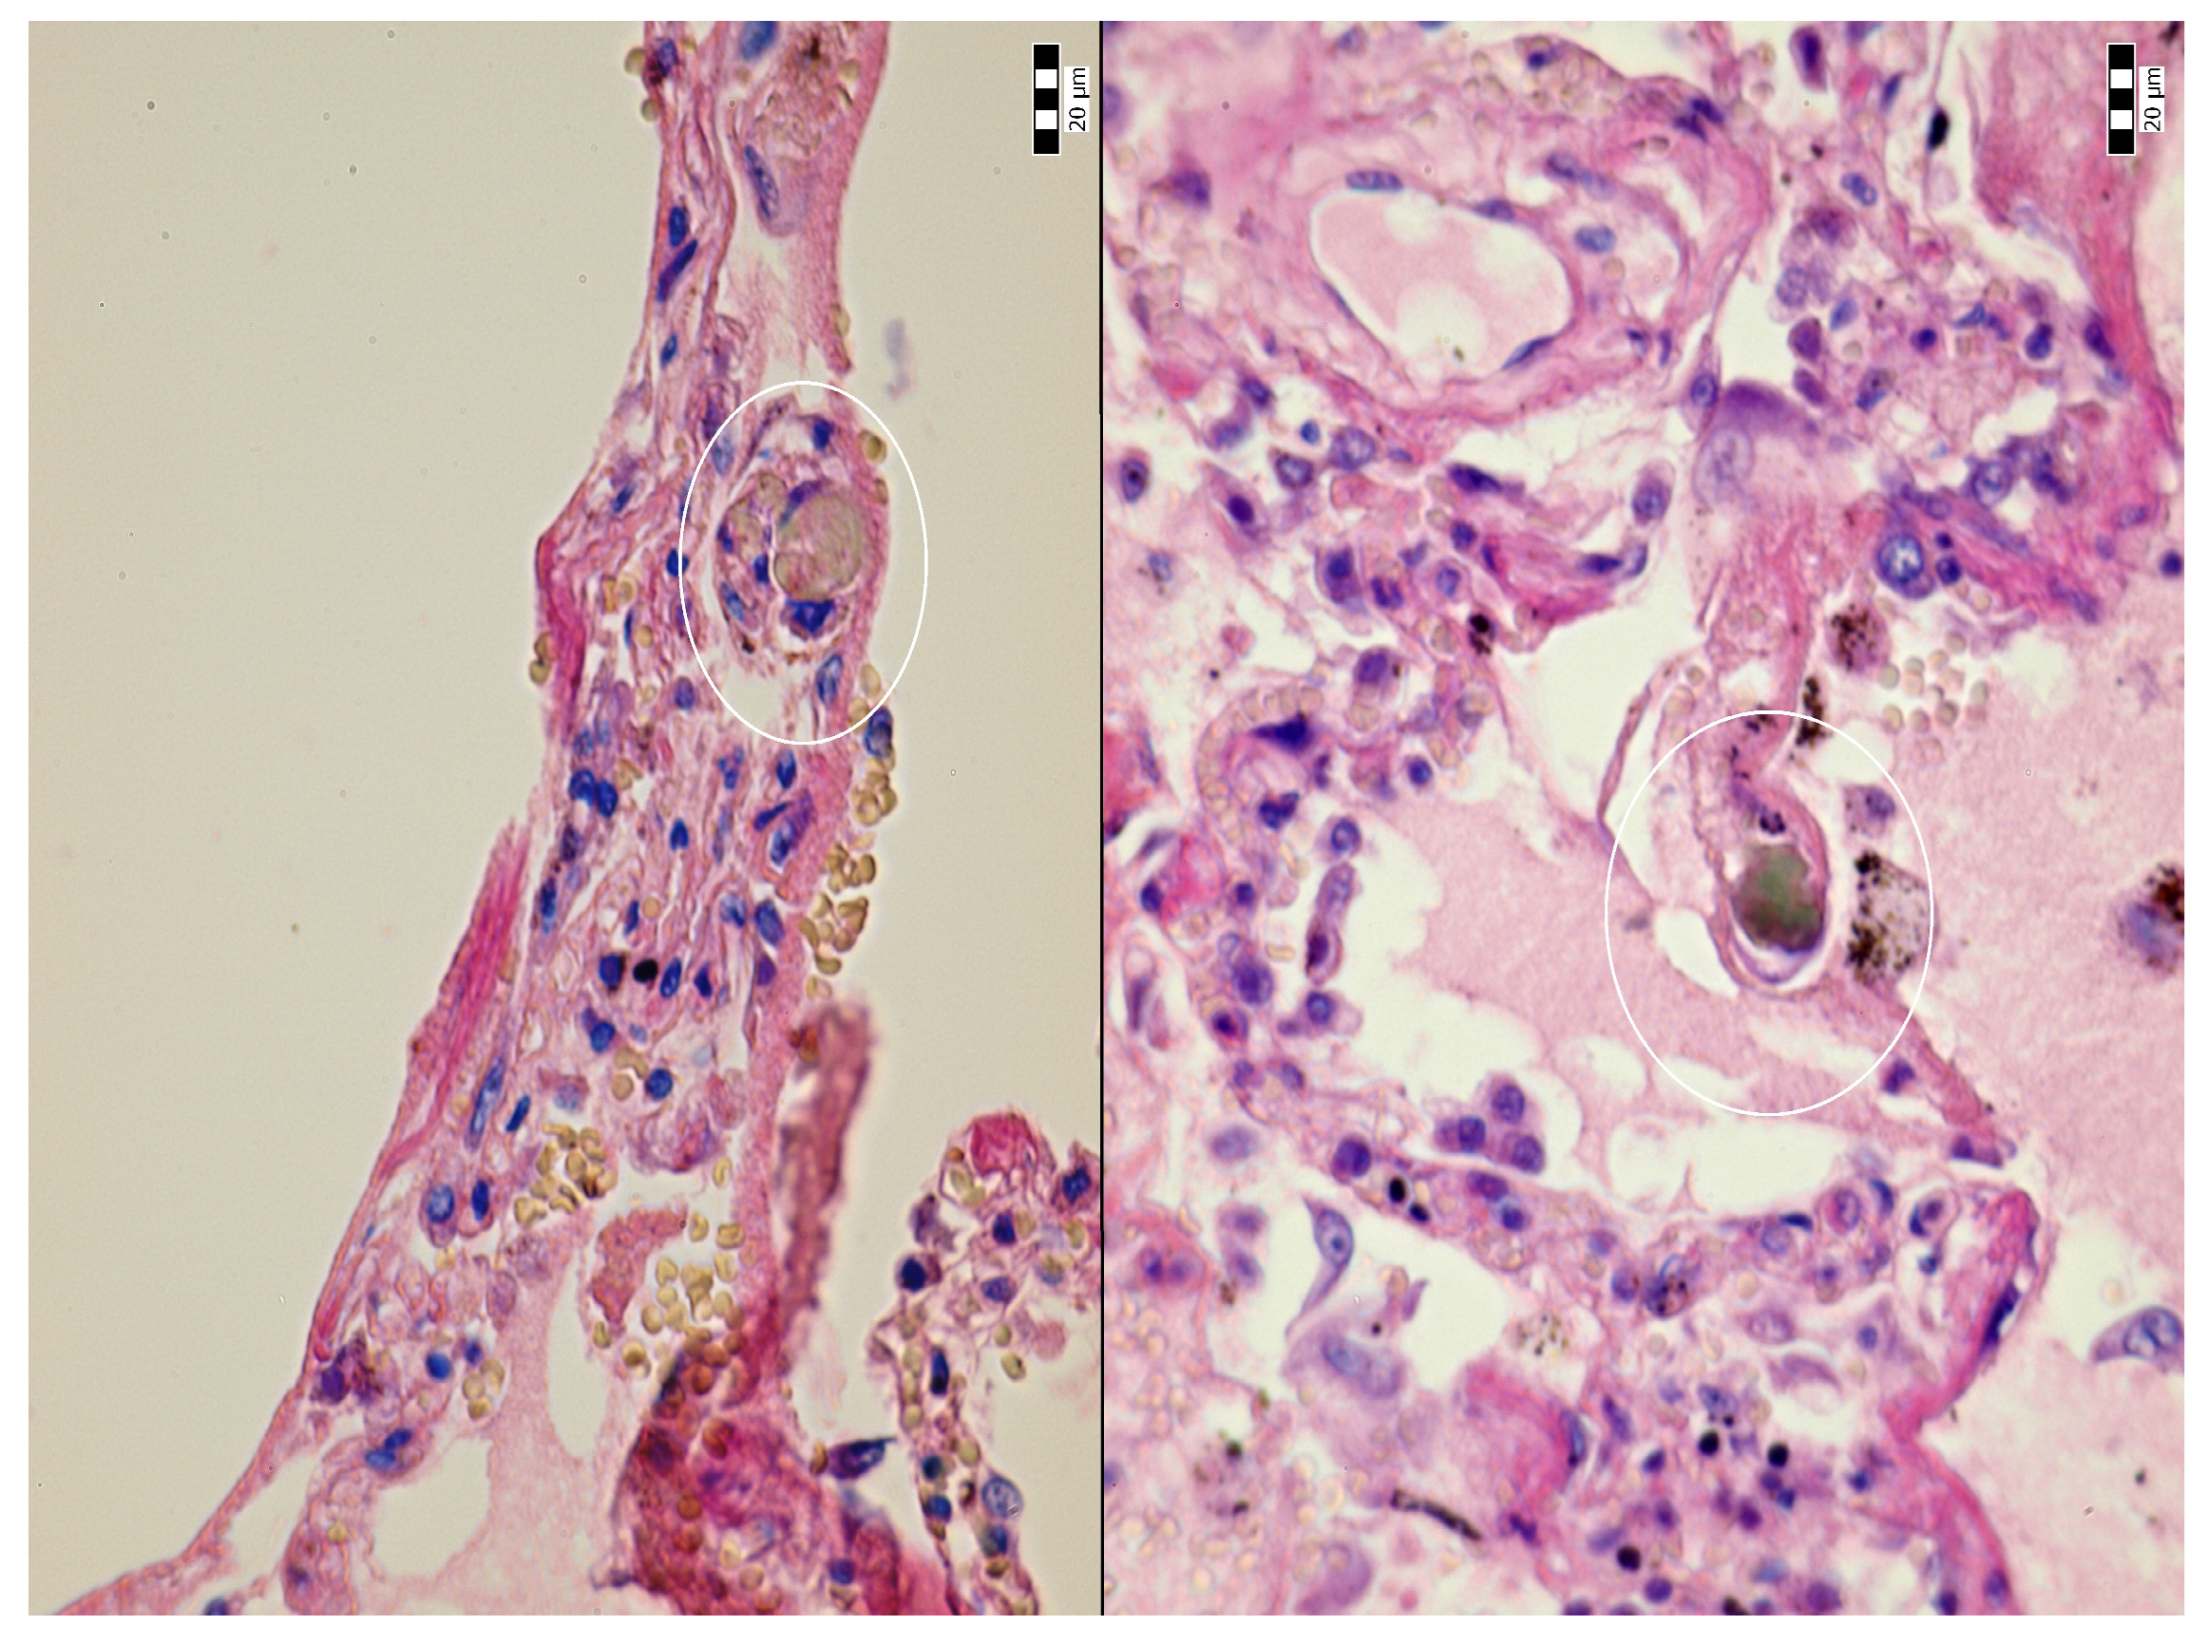

2. Case Description